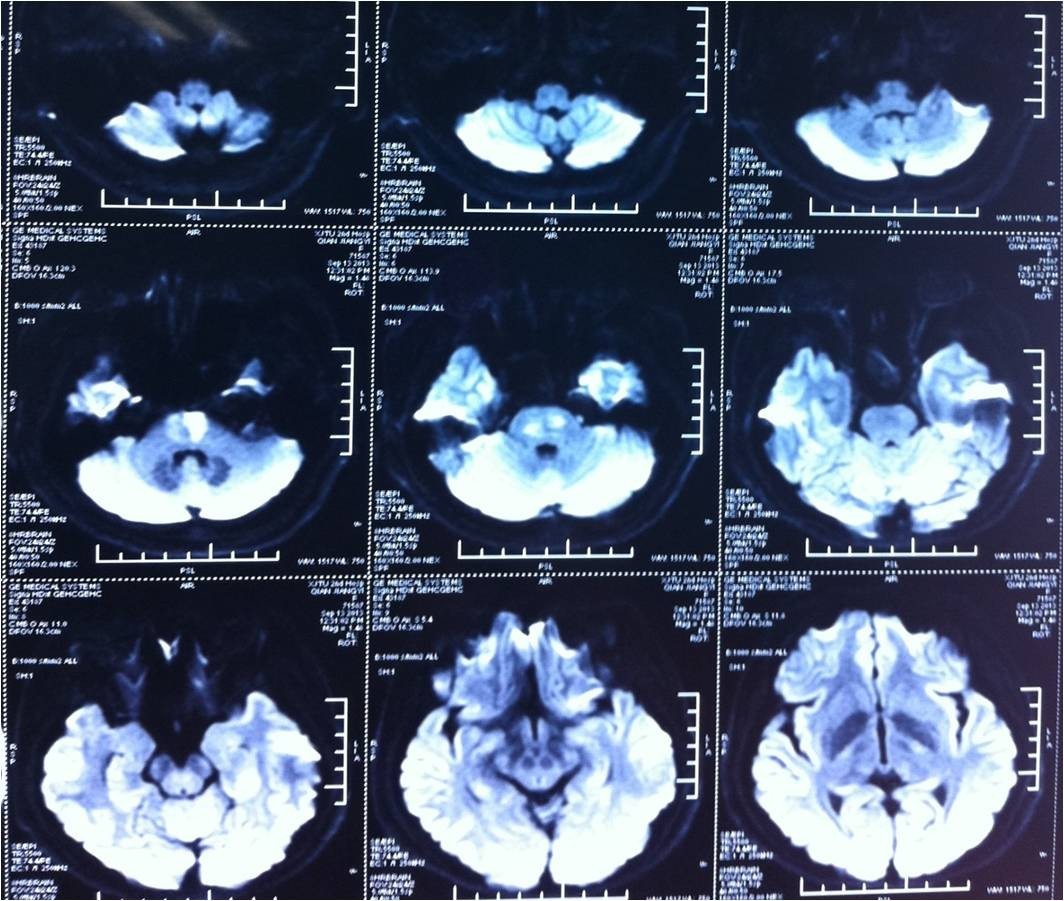

术前

3